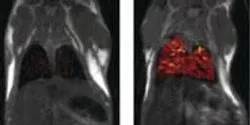

In a study of 1,600 chickens under controlled feeding, a research team analyzed liver samples from birds treated with Rox, a common feed supplement